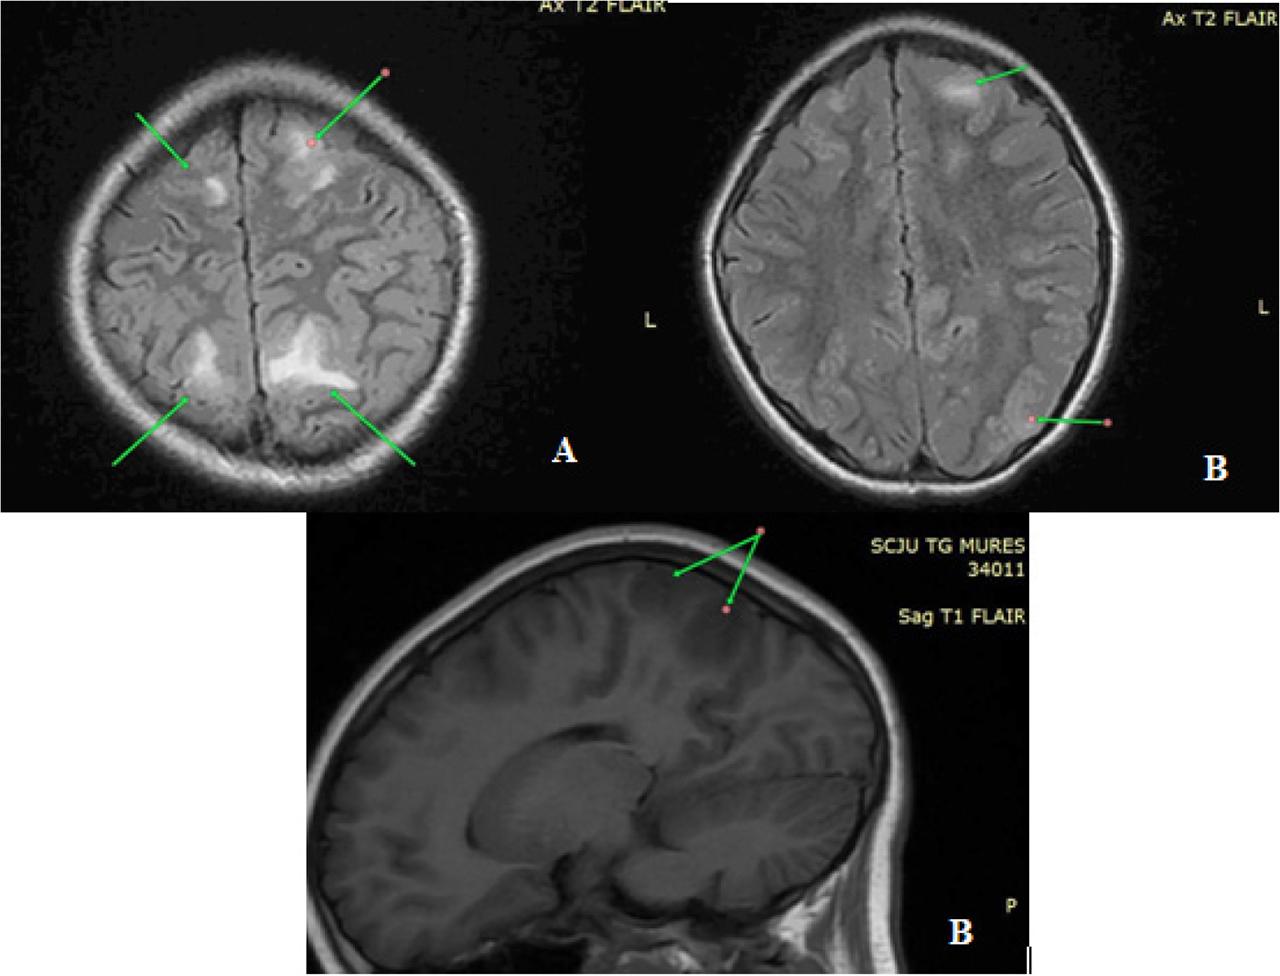

Fig. 2.